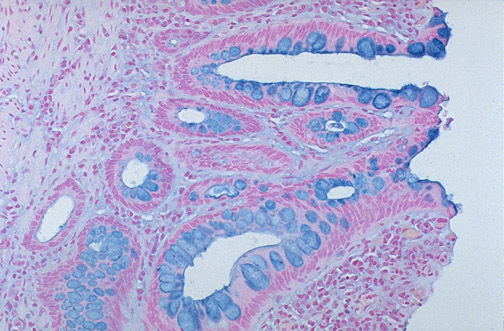

The goblet cells of the gastrointestinal tract are filled with abundant acid mucin and stain pale blue with this Alcian blue stain.